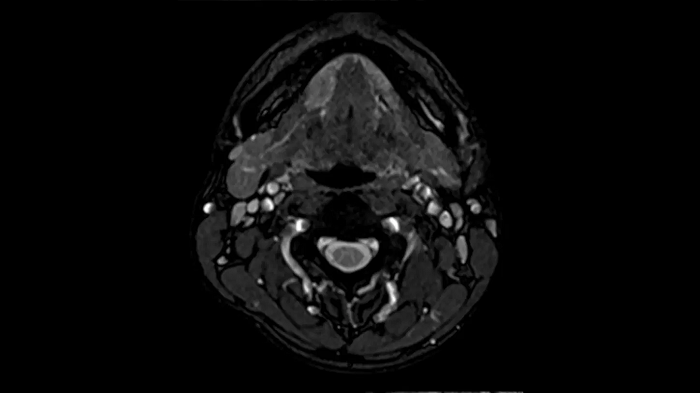

Neck

Excellent soft tissue contrast in the neck

An all-inclusive soft tissue investigation in the head with outstanding image quality for T1, T2, and diffusion contrast.

MAC-ID: 7aaaa0158.

MAC-ID: 7aaaa0158. Image Credit: Siemens Healthineers